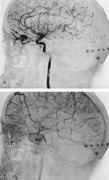

As noted, multiple saccular aneurysms of the carotid or vertebrobasilar system occur 20% to 30% of the time, frequently with identical or mirror sites found in the left-sided and right-sided circulations. Most aneurysms arise from the carotid system on the anterior communicating, middle cerebral, and internal carotid arteries, or they arise in the region of the origins of the posterior communicating arteries (Fig. 1A). Only some 5% of saccular aneurysms arise on the vertebrobasilar system (Fig. 1B).

Fig. 1. Common aneurysm sites in lateral (A) and basal (B) views. Numbers indicate percentage of aneurysms in each location. ACoA, anterior communicating artery; MCA, middle cerebral artery; ICA, internal carotid artery; PCoA, posterior communicating artery; PCA, posterior cerebral artery; VA, vertebral artery; BA, basilar artery. (Data from Krayenbuhl O: Kassifikation and Klinische Symptomatologie der zerebralen Aneurysmen. Ophthalmologica 167:122, 1973).